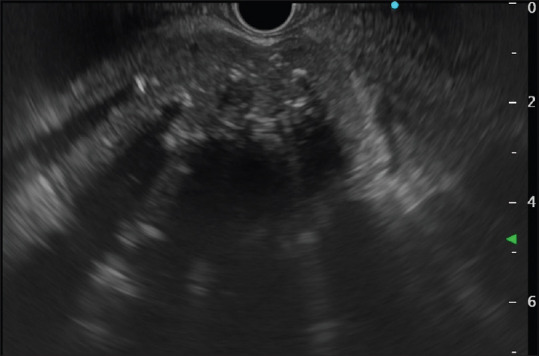

Castleman disease is a nonmalignant, lymphoproliferative disorder. Unicentric disease type involves a single enlarged lymph node or nodal regions, and multicentric disease involves multiple lymph node site involvement. We present a case of 26-year-old young female presented to outpatient with complaint of generalized weakness and abdominal pain for last 2 months. Her imaging included positron emission computed tomography which showed soft-tissue mass along the body of pancreas. Endoscopic ultrasound done showed nodal mass with extensive calcification and doppler endoscopic ultrasound showing arborising vessels. Fine needle aspiration cytology (FNAC) and biopsy taken showed lymphoid cells and diffuse hyaline material. After suboptimal response to chemotherapy regimen, she underwent open laparotomy and excision of the retroperitoneal mass.

Castleman病是一种非恶性淋巴增生性疾病。单中心性疾病类型涉及单个肿大的淋巴结或淋巴结区域,多中心性疾病涉及多个淋巴结部位。我们报告了一例26岁的年轻女性,在过去的两个月里,因全身无力和腹痛而门诊就诊。她的成像包括正电子发射计算机断层扫描,显示胰腺体部的软组织肿块。内窥镜超声检查显示结节性肿块伴广泛钙化,多普勒内窥镜超声波检查显示树枝状血管。细针抽吸细胞学检查(FNAC)和活检显示淋巴细胞和弥漫性透明质。在对化疗方案反应不佳后,她接受了剖腹手术和腹膜后肿块切除术。